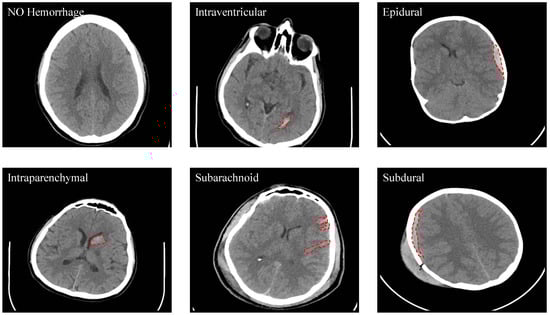

| Total number of subjects | 82 | Sex (Male, Female) | 46 M, 36 F |

| Age (yr) | 27.8 ± 19.5 | Age range | 1 day–72 years |

| Number of subjects (age<18 years, age≥18 years) | 27,55 | Number of subjects with ICH | 36 |

| Number of subjects with IVH, IPH, SAH, EDH, and SDH | 5,16,7,21,4 | Number of subjects with skull fracture | 22 |

| Intraventricular | 24 | Epidural | 182 |

| Intraparenchymal | 73 | Subdural | 56 |

| Subarachnoid | 18 | No Hemorrhage | 2173 |